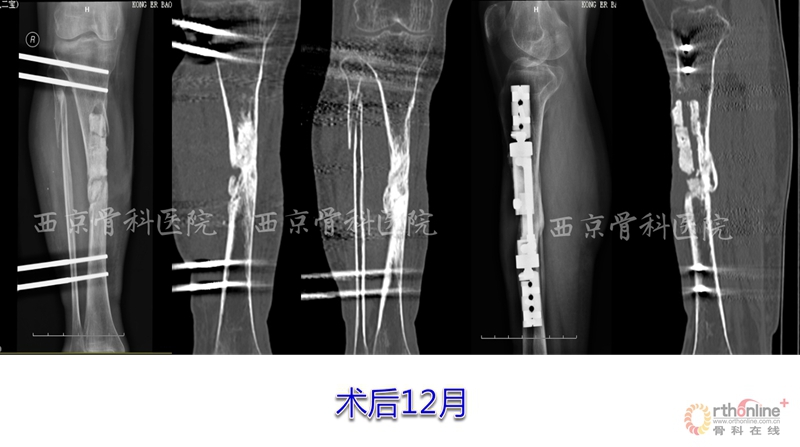

术后,他们按照组织工程再生骨临床转化应用方案定期进行血液指标、免疫指标和影像学指标的检测复查,患者术后3个月即可扶拐下地行走,术后6个月可弃拐逐步下地负重行走,12个月拆除已使用了2年的外固定支架,行走及下肢关节活动如常,恢复了正常的生活与劳动能力。

如今,术后22个月的患者已可快步行走、上下楼梯和搬移重物,其日常活动与重体力劳动与常人无异。